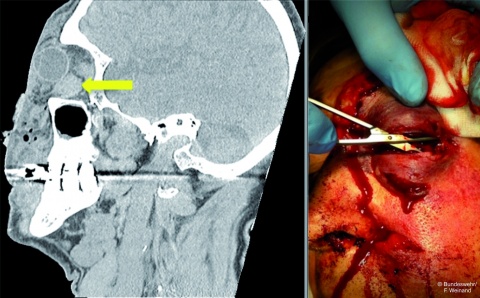

verursacht durch

para- und retrobulbäre Blutungen

(Pfeil im CT-Bild links) in die abgeschlossene

Orbita (Kompartment)

führt zu einer massiven

Durchblutungsstörung des

Auges. Ohne rasche Druckentlastung

durch laterale Kanthothomie

und inferiore Kantholyse

(Bild links) innerhalb der ersten

Stunde ist die Funktion des

Auges meistens verloren.